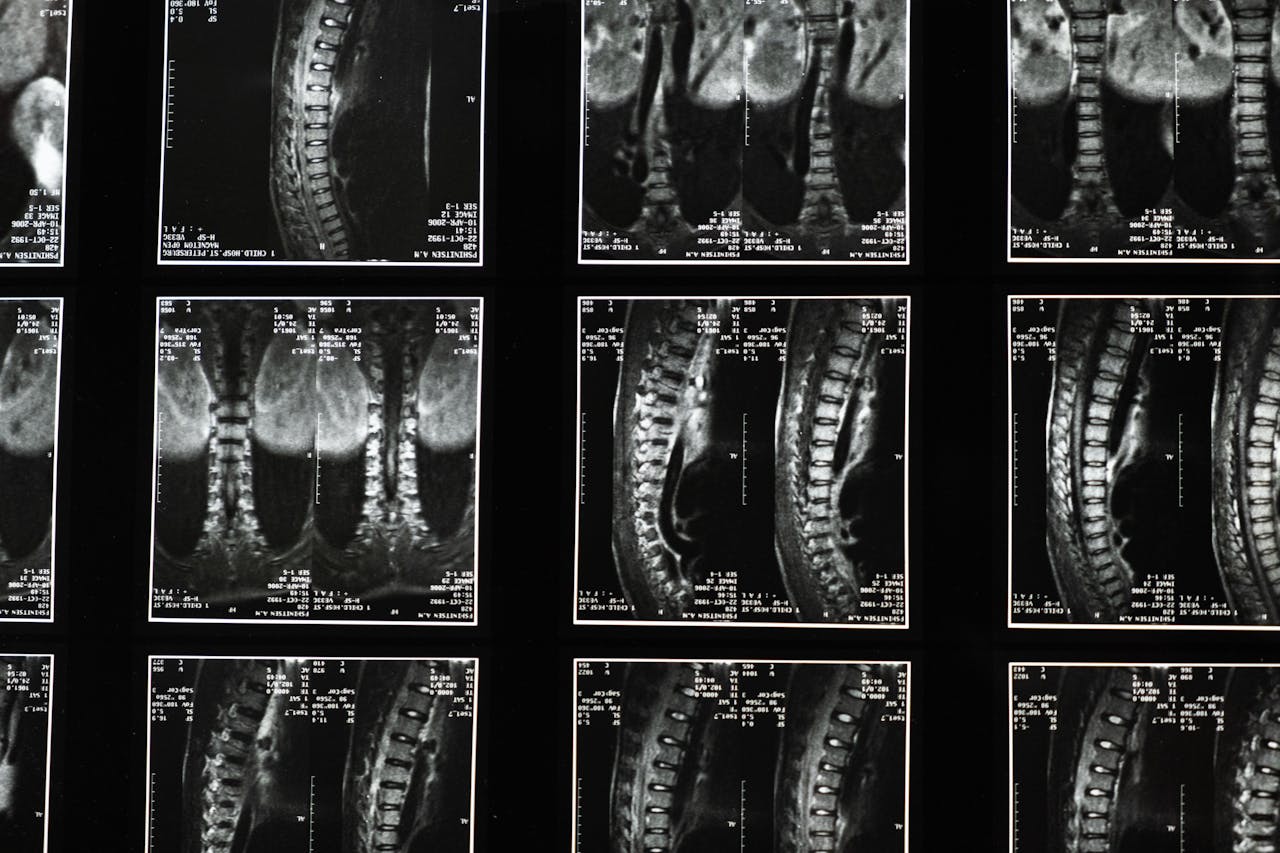

With specialized services in post-operative recovery, chronic pain management, and neurological physiotherapy, our experienced team creates customized treatment plans. Our dedication to patient care has earned us recognition in the community, making us a go-to resource for effective rehabilitation solutions.